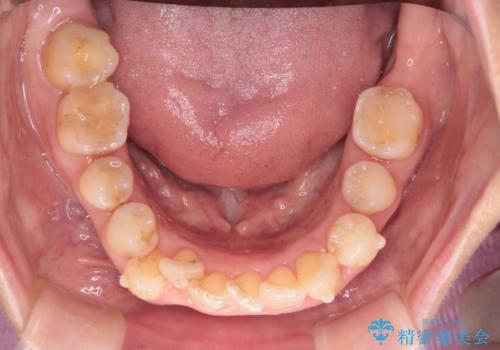

今回の治療では、右上5番の抜歯スペースを活用して八重歯(3番)を後方へ誘導しました。

インビザライン独自の3Dシミュレーションに基づき、必要な歯だけをピンポイントで動かすことで、抜歯を伴う大きな移動も効率的に行いました。

治療の結果、突出していた八重歯はきれいなアーチに収まり、左右対称でバランスの取れた口元になりました。インビザラインは自由に取り外しができるため、治療期間中も口腔内を清潔に保ちやすく、患者様もストレスなく治療を完了されました。